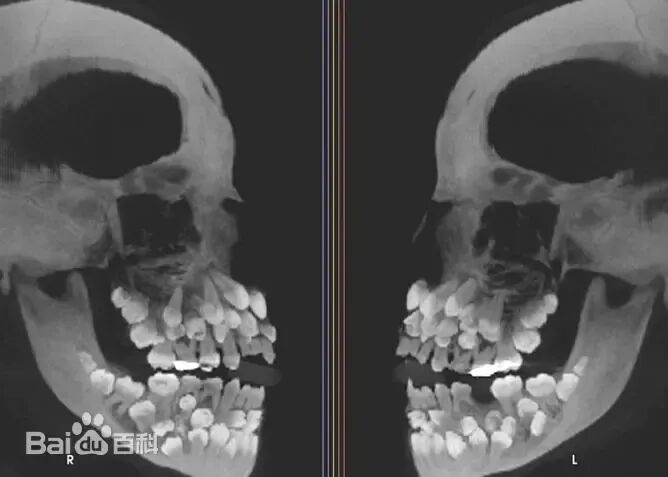

还有基因觉得牙齿顺着下颌骨方向排列不一定对,于是把牙齿在口腔内重新分布,看看好不好用。

这照片可不是P的,甚至这样的牙齿也不是一个两个人有,而是不少人有,形状略有区别,但在口腔内重新分布的性质是一样的。

就这牙,要是被咬上一口,走近科学能连拍10集,因为光凭咬痕,那是真分辨不出来到底是人咬的还是啥生物咬的。